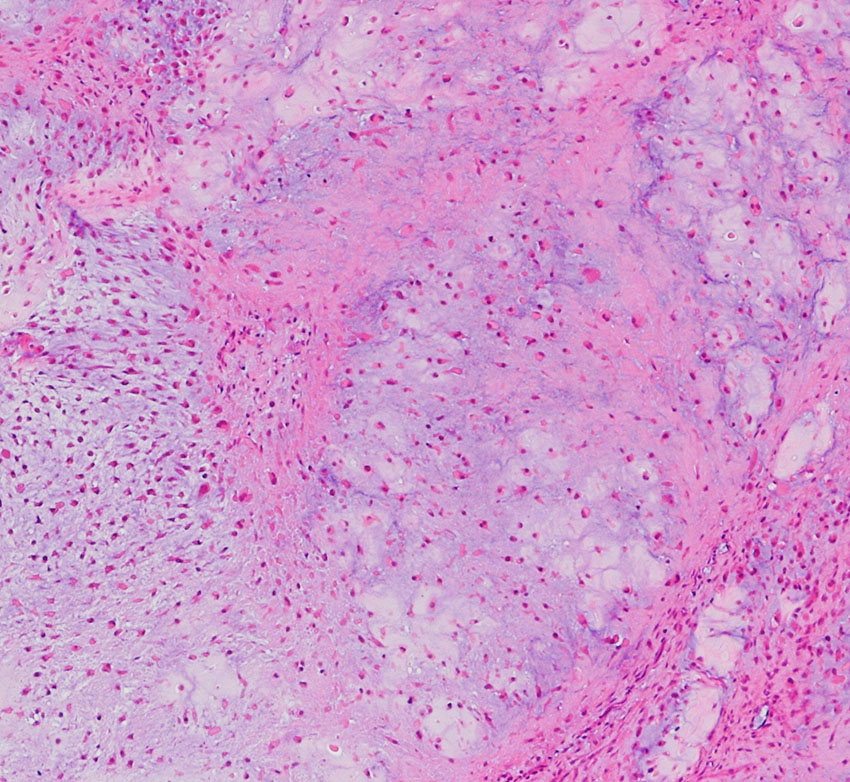

低悪性度軟骨肉腫の病理像 grade 2 chondrosarcoma

背景は好塩基性の軟骨基質(粘液状 myxoid,軟骨様 chondroid)です。好酸性胞体をもつ異型紡錘形ないし上皮様細胞が多結節状に増殖しています。細胞密度はやや高い部分もあり,核は濃縮され大小不同や2核の細胞も見られます。MIB-1 index 3%